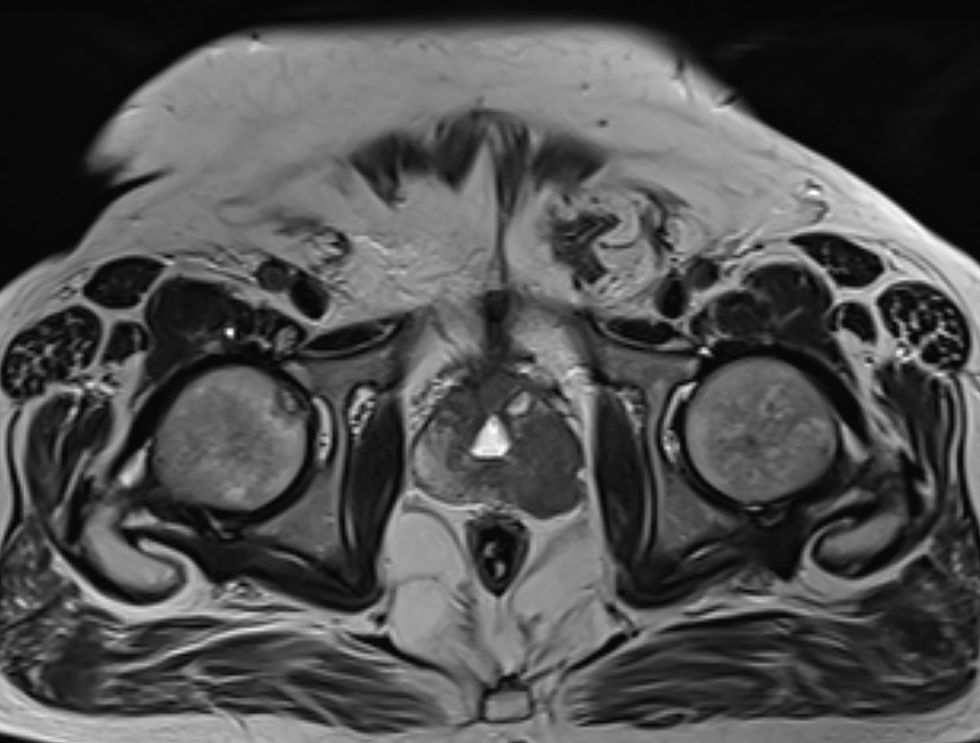

Prostate cancer is the most widespread cancer among males in the UK

Prostate cancer strikes 63,000 British men every year and claims 12,000 lives, making it the most widespread cancer among males in the UK.

Despite these stark figures, it remains the only major cancer that does not have a screening programme in place.